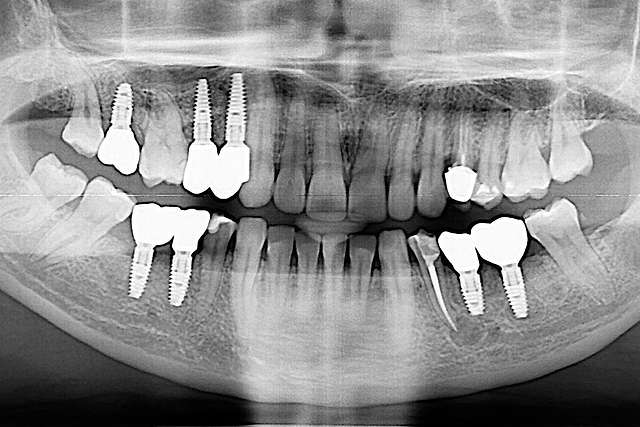

Dental implants are treatments designed for teeth that we can no longer save. Dental implants rely on the principle of osseointegration, or in other words, on the implant being integrated in the bone. For a long period of time, this was the main objective of the industry. Osseointegration, placing implants in relation to bone. Today , we know that osseointegration is extremely predictable and we focus on key elements that can make the difference in the quality of the end result.

Guided surgery, for one, facilitates an ideal pre-planned position, in relation to available bone, and even more important, in relation to the future implant supported crown. Guided surgery translates into increased precision, which means safer surgeries, reduced surgery time, and reduced trauma. Also the focus of these types of treatments is shifted towards tissue reconstruction, which on the long run, has a far greater impact esthetically and biologically. Tissue stability means implant longevity. This case is a relevant example for this type of approach towards implant dentistry.